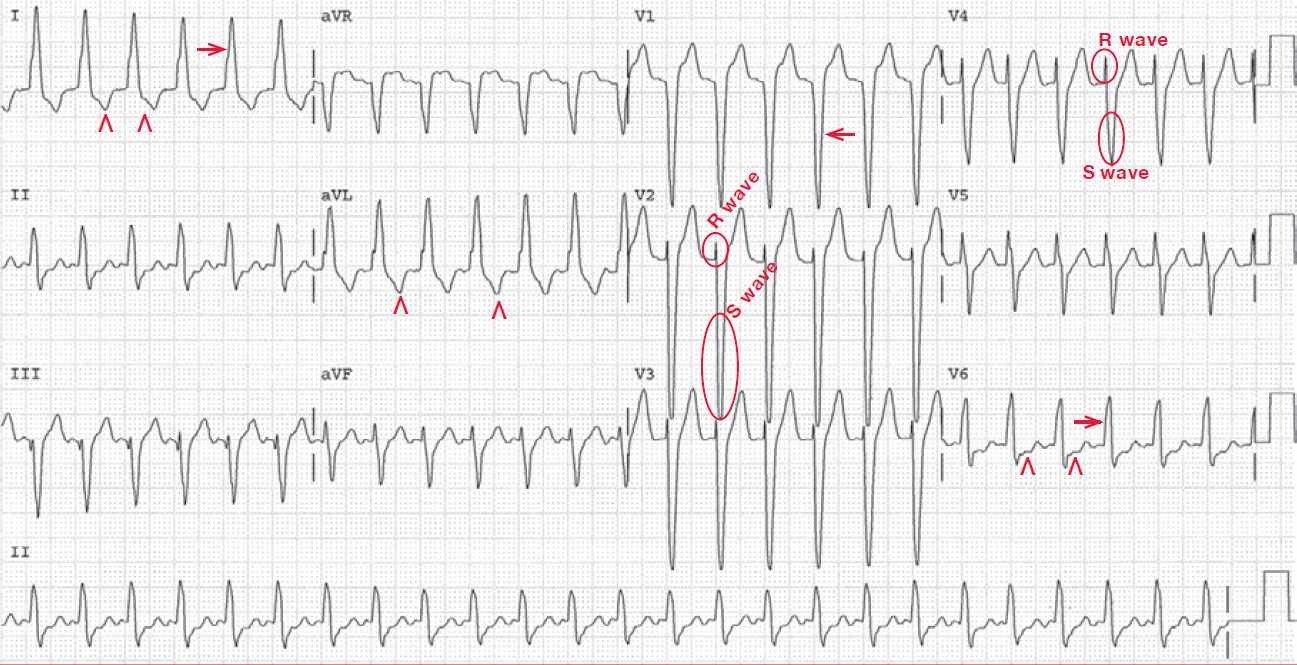

The ECG shows a regular rhythm at a rate of 150 bpm. There are no P waves seen before or after any of the QRS complexes. The QRS complex duration is increased (0.16 sec), and hence this is a wide complex tachycardia, which may be either ventricular tachycardia or a supraventricular tachycardia with aberration.

The morphology is that of a typical left bundle branch block with a tall, broad R wave in lead I (→) and V6 and a deep QS complex in lead V1 (←). There are ST-T wave changes seen in leads I, aVL, and V6 (^). If this is a left bundle branch block, then these are secondary to the left bundle branch block. If this is a ventricular tachycardia, then the T-wave abnormalities reflect the presence of a ventricular complex.

It is not clear from this ECG if this is a supraventricular tachycardia or a ventricular tachycardia. However, there are R/S complexes in leads V2–V4, the R wave is wider than the S wave (R/S < 1), and the R wave is less than 100 msec. As the initial forces are normal, while it is the terminal portion of the QRS complex that is wide, this morphology is consistent with a supraventricular tachycardia with a left bundle branch block aberrancy.

The absence of recognizable P waves establishes this as a no-RP tachycardia and the most common arrhythmia presenting in this fashion is an atrioventricular nodal reentrant tachycardia.